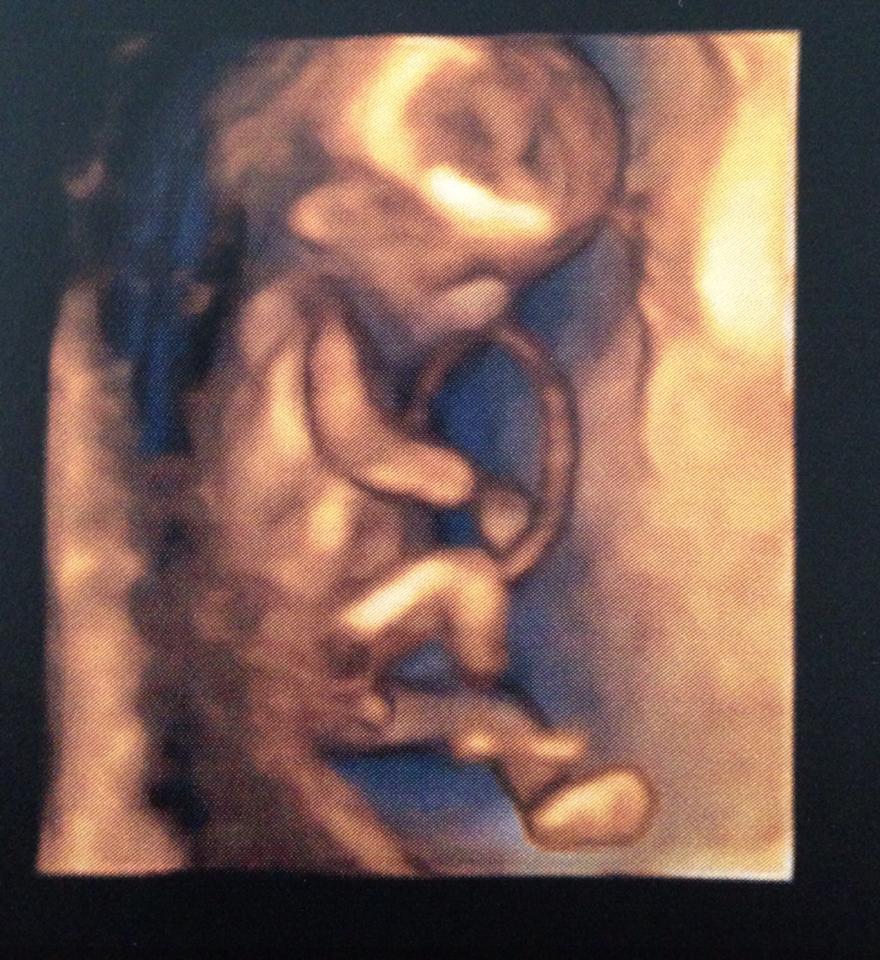

I had a 13 week scan last week, hoping to get a good nub shot. Unfortunately bub wasn't co-operating and wouldn't straighten out to get a shot. We did however get a 3D shot between the legs and the tech was confident it was a little boy.

I would love other opinions to see if you think she was right or if it's too early to tell.

I've included both photos.